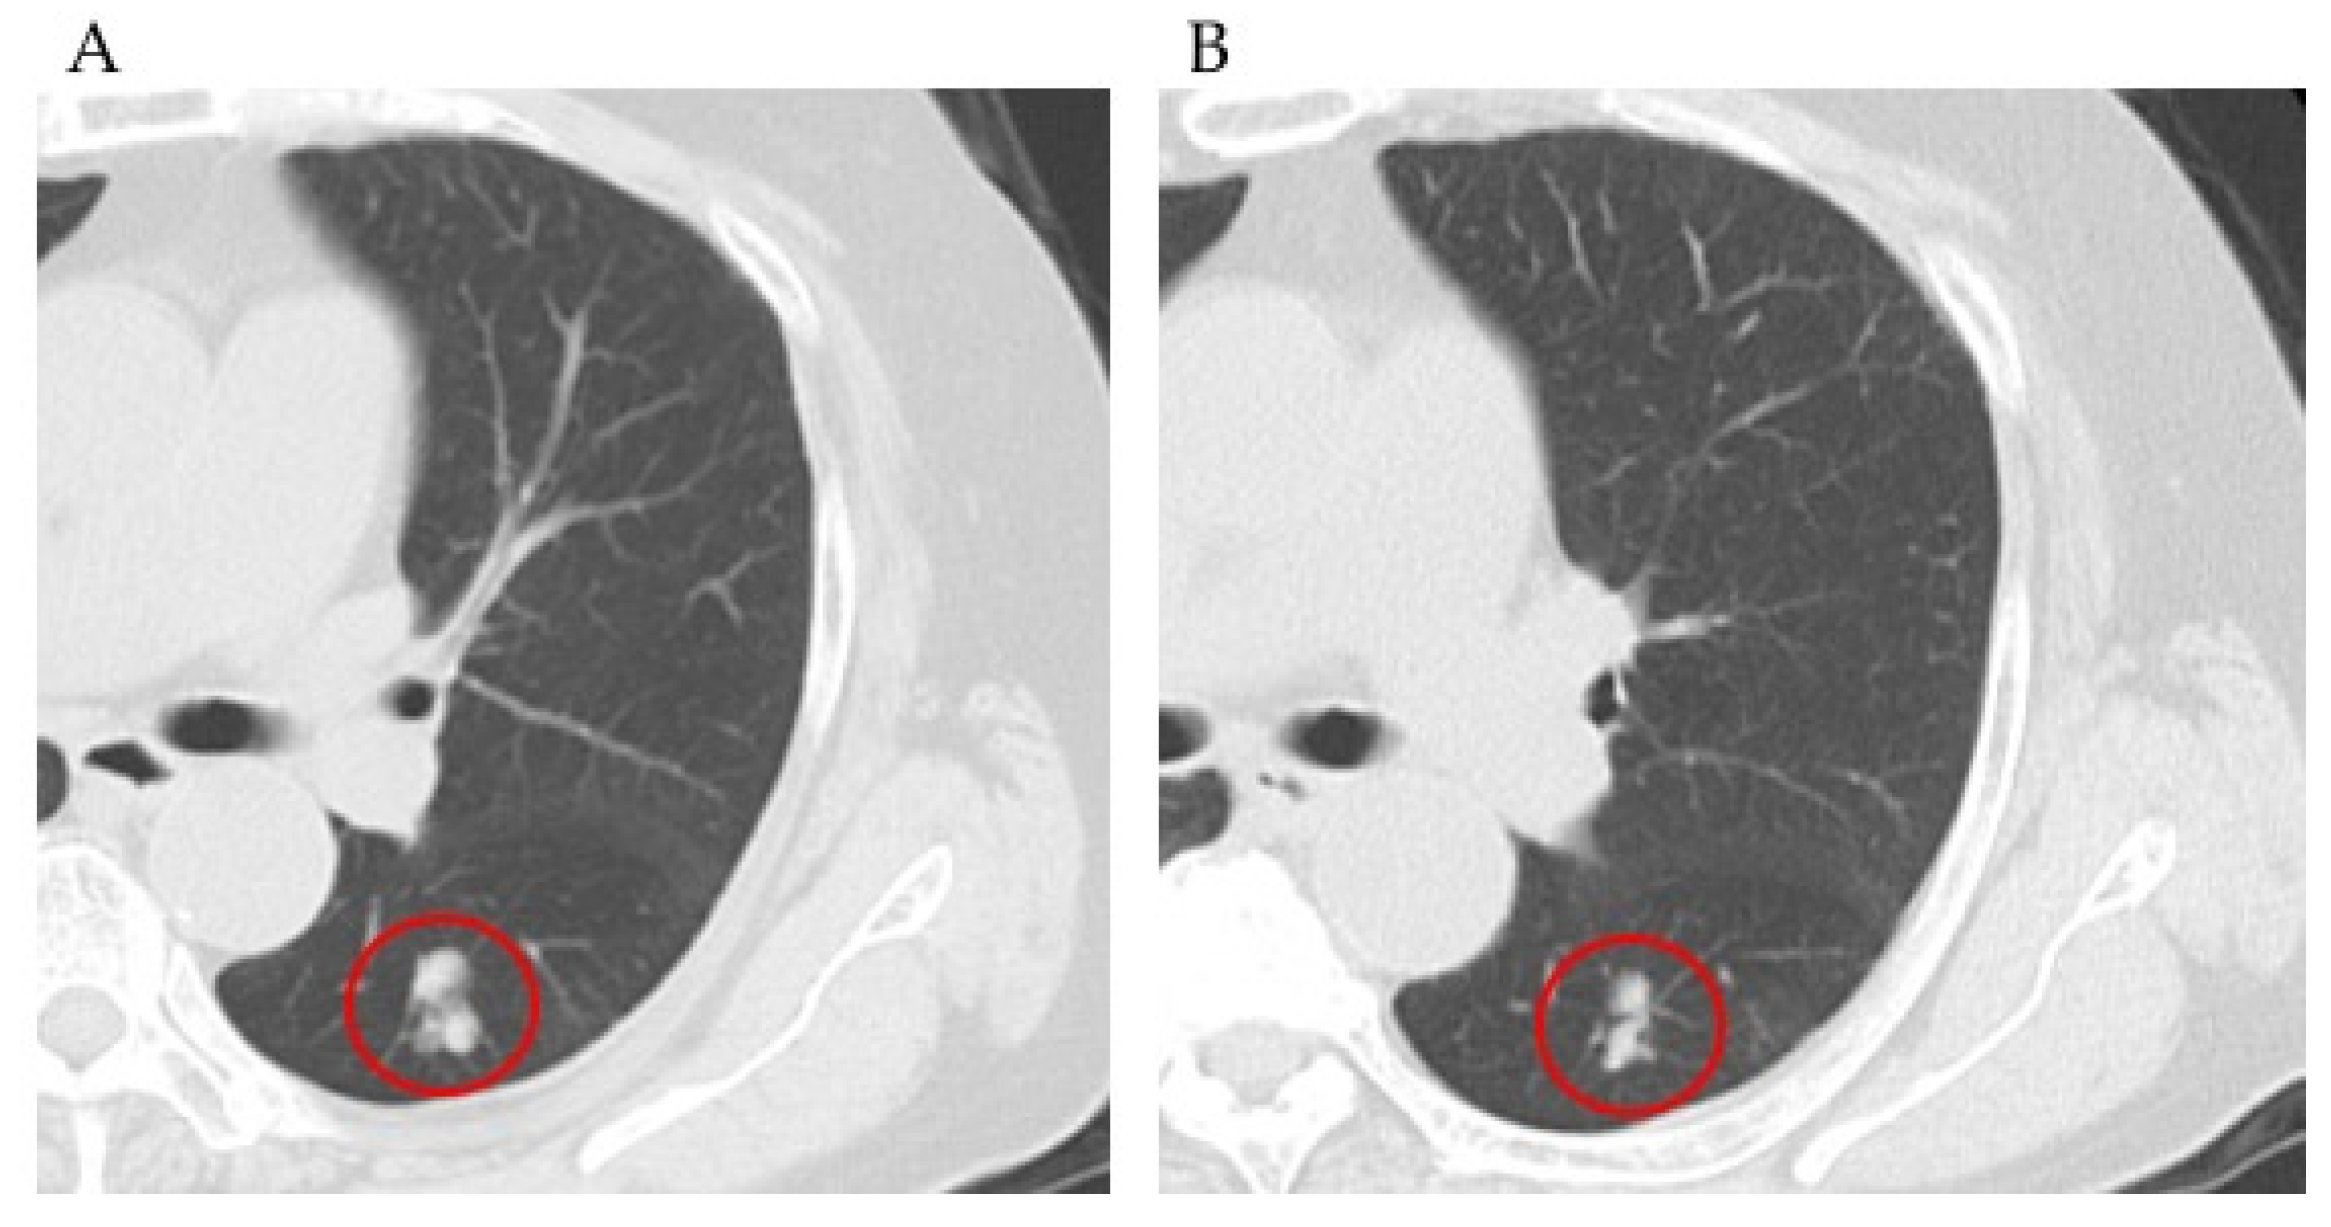

2.4.2. Case 2

2.4.3. Case 3